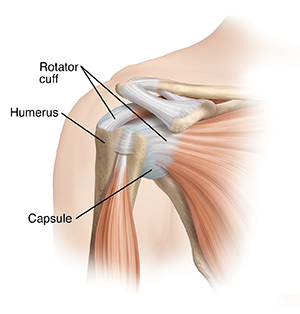

A healthy, stable shoulder

The head of the arm bone (humerus) rests in a socket (glenoid), much like a golf ball fits on a tee. Parts of the joint called stabilizers hold the humeral head and glenoid together. These include a sheet of ligaments and other tough fibers called the capsule. This encloses the humeral head and glenoid.

The leading cause of instability is an injury that forces the humeral head out of its socket. If the humerus pushes completely out of the socket, it’s called a dislocation. If it only pushes partially out, it’s called a subluxation. In both cases, the injury stretches or tears fibers in the capsule. It can also damage other parts of the joint. This makes the humeral head more likely to slip out of the glenoid again.